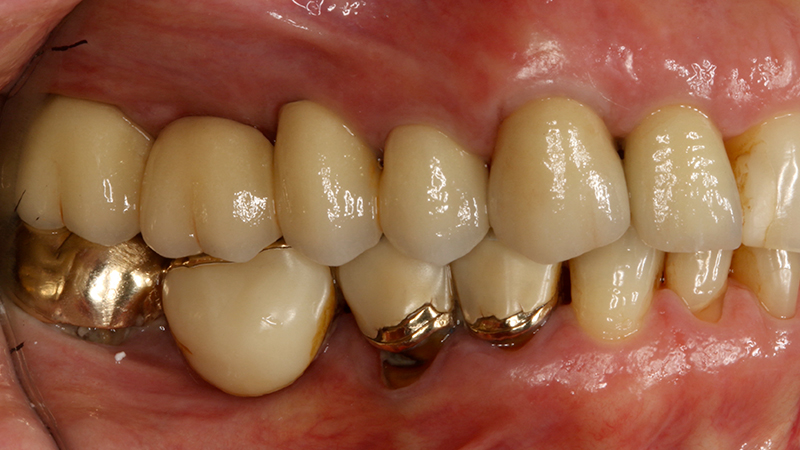

La paziente, di 68 anni, buona salute generale, presentava un grave problema al ponte 17-15-14 con dolore alla masticazione, mobilità e grave perdita ossea su 17 e 12 (Figs. 1, 2, 3).

La finalizzazione del caso avveniva con protesi in metallo-ceramica passivata su cappe conometriche in bocca (Figs. 24, 25, 26, 27, 28, 29, 30, 31, 32) e radiografie finali ad un anno dal carico (Figs. 33, 34).

Applicazione ponte 17-14 in metallo ceramica su cappette conometriche passivate in bocca mediante cemento

Fig. 24 - Applicazione ponte in metallo ceramica su cappette conometriche passivate in bocca mediante cemento Multilink Hybrid e risultato finale

Applicazione ponte 17 - 14 in metallo ceramica su cappette conometriche passivate in bocca mediante cemento Multilink Hybrid e risultato finale

Fig. 25 - Applicazione ponte 17 - 14 in metallo ceramica su cappette conometriche passivate in bocca mediante cemento Multilink Hybrid e risultato finale